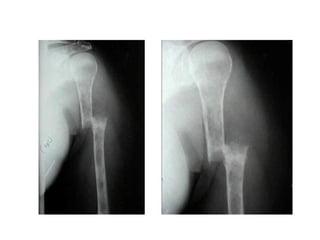

Ossos e Articulações

● Hemartroses

● Dor óssea

● Edema articular

● Úlceras de perna

● Gota secundária

Hematoma e hemartrose